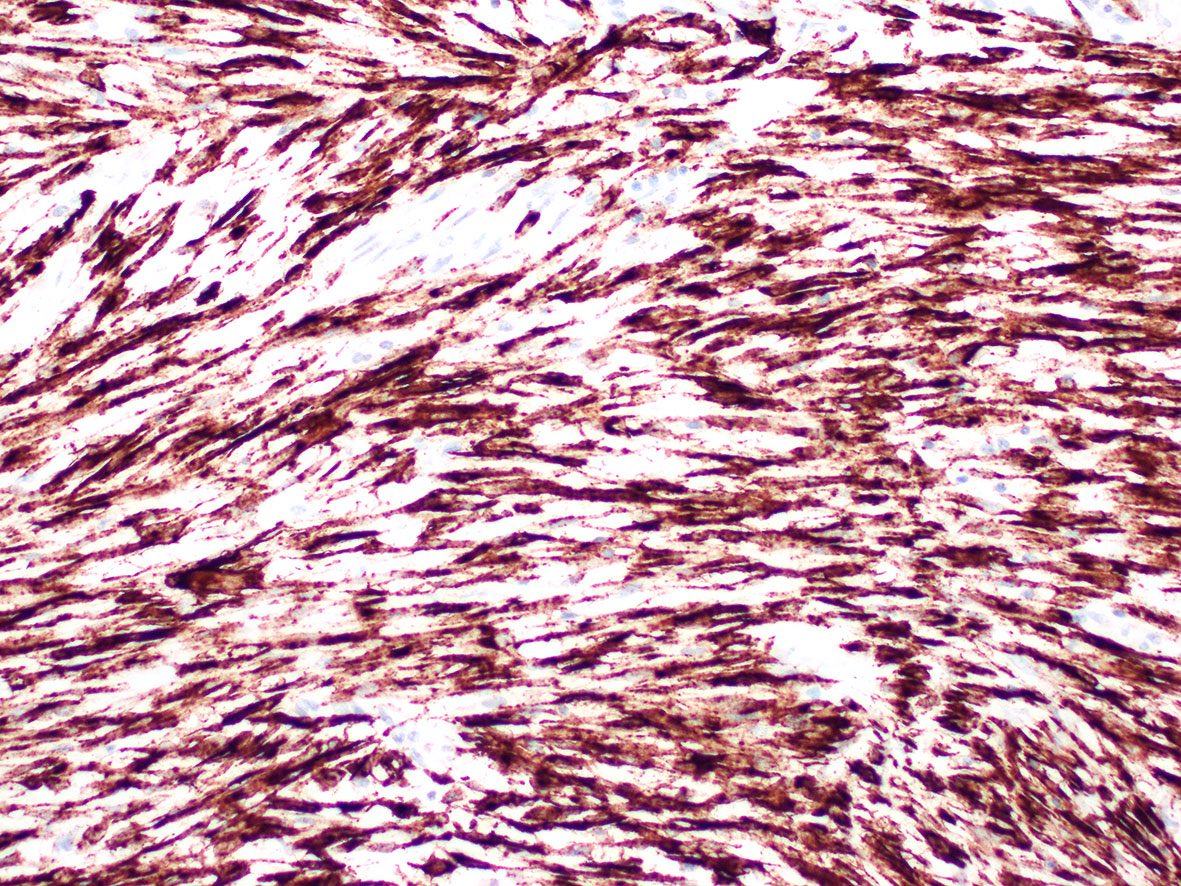

Microscopic (histologic) images

Contributed by A. Cristina Vargas, M.B.B.S., Ph.D., Patricia Guzman, M.D., Fiona Bonar, M.B.B.Ch., Alison Cheah, M.B.B.S. and Martin Jones, M.B.B.S.

Practice question #1

What is the expected diagnosis for a uterine spindle cell tumor with this histological appearance? The tumor displayed focal smooth muscle expression, strong ALK overexpression on IHC and an ALK translocation was confirmed by FISH.

- Endometrial stromal sarcoma

- Epitheliod myofibroblastic sarcoma

- Inflammatory myofibroblastic tumor

- Leiomyoma

- Spindle cell tumor (S100+ / SOX10- / CD34+) with ALK translocations

Practice answer #1